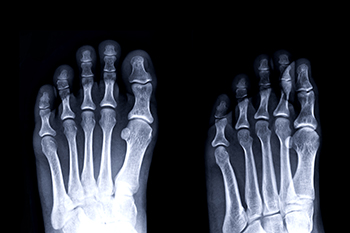

The foot is a complex structure made to support movement, balance, and weight. It is built from key bones, such as the talus, calcaneus, and cuboid, along with many smaller bones that work together through a network of 33 joints. Numerous tendons and ligaments connect these bones and allow the foot to move smoothly while providing strength and stability. These parts work as a unified system to help you stand, walk, and adapt to different surfaces. A podiatrist can evaluate how well your foot structures are functioning, identify sources of pain, and recommend treatments that restore comfort and mobility. If foot pain is interfering with your daily activities, it is suggested that you consult a podiatrist who can determine the cause and offer effective relief and treatment solutions.